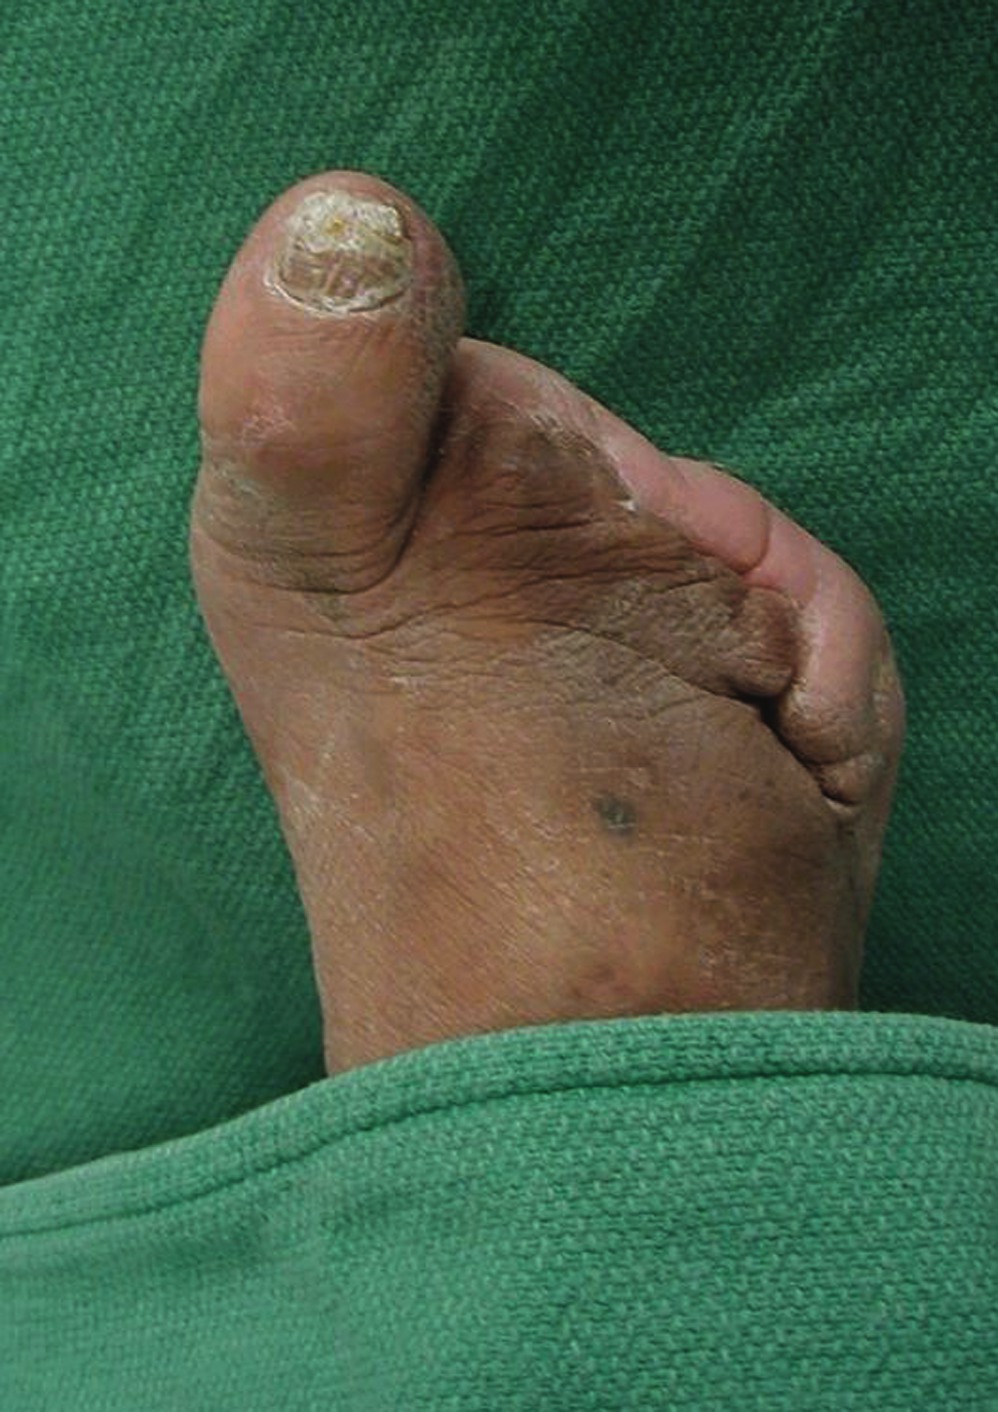

A 58-year-old patient presents with a 20-year history of type 2 diabetes. His control has been mediocre with hemoglobin A1c levels around 8.5 percent. He has been treated for hypertension and is being monitored by cardiologists. The patient has a history of chest pain but no events of myocardial infarction or cerebrovascular accidents (CVA). He developed a pressure ulceration of his fifth toe that led to osteomyelitis. Preoperative indices for healing were borderline. Surgeons amputated the toe but it failed to heal. Peripheral vascular surgeons performed an angioplasty and the patient’s foot perfusion improved. He did require an amputation of the adjacent fourth toe due to progressive necrosis of the wound edges from the previous amputation. This wound also dehisced but improved slowly over time, probably due to the vascular intervention. In the meantime, his chest pain became worse and he required a coronary angioplasty. The patient also required prolonged local foot wound care to achieve healing. After two foot procedures, a vascular intervention, cardiac complications, lengthy wound care and a disability that lasted over a year, the foot finally healed and the patient returned to work in his previous occupation. He wears accommodative shoes and sees his podiatrist for regular follow-up visits. This case illustrates a difficult protracted course of limb salvage but nevertheless, the patient successfully returned to productive community activity. In contrast, a 62-year-old patient had a similar diabetes history but more vascular problems and evidence of the early stages of renal failure. He had a history of myocardial infarction and coronary artery angioplasty before a minor injury to his second toe resulted in distal cyanosis and ischemic pain. The toe was cool, there was no break in the skin and there were no pulses in the foot. Surgeons performed peripheral vascular stenting and the patient’s ankle brachial artery indices improved. However, the aforementioned toe remained cool and painful. Despite a second toe amputation, the wound still failed to heal. The vascular service performed yet another angioplasty as well as extensive debridement of bone and soft tissue, yet little improvement in the wound occurred. Amputation to the Syme’s level was recommended but the patient was adamant about making more efforts to try to save more of the foot. He proceeded to undergo a transmetatarsal amputation. The amputation site presented a non-viable wound that clinicians treated for over a week before the patient demonstrated signs of progressive necrosis and sepsis. Finally, the patient underwent a transtibial amputation. Six weeks later, surgeons fitted the patient with a prosthesis and he began rehabilitation. Although he took early retirement, the patient has returned to independent community ambulation. Had the surgeons performed the transtibial amputation after the failed toe amputation, three operations would have been eliminated from this patient’s five-stage below-knee amputation. His case illustrates the fact that in spite of our best efforts, all limbs with diabetic complications are not salvageable. Both patients had low normal levels of serum albumin at approximately 3.0 gm/dl. Their total lymphocyte counts were both above 1,700. Their ankle brachial indices were about 0.3 before their vascular procedures and 0.45 afterward. They both had heart disease but who had more severe heart disease? The 58-year-old patient had worse control but the 62-year-old patient had early renal disease. If one measured the degree of control, nutritional status, renal function and cardiac function, would a significant difference between the two in any of these parameters be predictive of their eventual outcome? Right now, we do not know but the fact that many limb salvage attempts fail suggests we should find out.